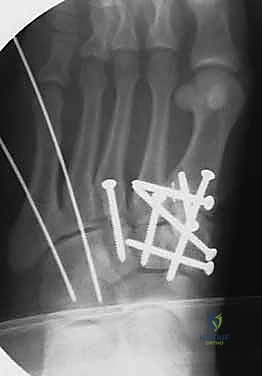

1. الرد المفتوح والتثبيت الداخلي (ORIF - Open Reduction and Internal Fixation)

هذا هو الإجراء الكلاسيكي والأكثر شيوعاً. يهدف إلى إعادة العظام إلى مكانها الطبيعي (الرد) وتثبيتها باستخدام معدات طبية (مسامير، شرائح، أو أسلاك) حتى تلتئم الأربطة والعظام.

خطوات العملية:

4. التثبيت (Fixation): يتم تثبيت العظام باستخدام مسامير معدنية خاصة (Solid or Cannulated Screws) تعبر المفاصل لتثبيتها بإحكام. في بعض الحالات، يتم استخدام شرائح معدنية صغيرة للحفاظ على الاستقرار.

5. مسمار ليزفرانك: الخطوة الأهم هي وضع "مسمار ليزفرانك" (Lisfranc Screw) الذي يمر من العظم المسماري الإنسي إلى قاعدة المشط الثاني، لتعويض وظيفة الرباط الممزق.

6. الإغلاق: يتم إغلاق الشقوق الجراحية بعناية تجميلية ووضع القدم في جبيرة لحمايتها.